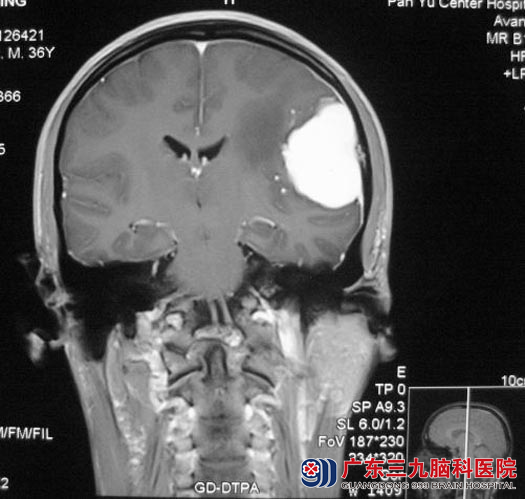

当地医院头颅MR检查提示:左侧颞顶部占位,考虑脑膜瘤,肿瘤直径约4.5cm,医生建议手术治疗。

6月6日,广东三九脑科医院综合神经外科 鲁明主任主刀,在全麻下行肿瘤切除术,额颞部硬膜色泽改变,已被肿瘤侵犯破坏,显微镜下见灰白色肿瘤组织,边界较清,部分脑膜与肿瘤粘连紧密,肿瘤切除后予病变硬膜一并切除,经过顺利。术后病理为:脑膜瘤(透明细胞型,WHO II级)。